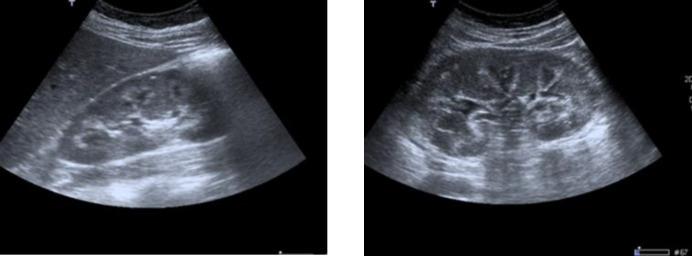

Furosemide is a drug widely used for several medical conditions and could be used without medical prescription. Furosemide-related nephrocalcinosis can occur regardless of age, although the risk is higher in premature infants. The defining characteristic of nephrocalcinosis is generalized calcium deposition in the kidney. The most useful imaging studies for evaluation are ultrasonography and computed tomography (more effective in detecting calcification).

A 32-year-old woman with a history of depressive syndrome was admitted for evaluation of fortuitously discovered nephrocalcinosis and hypokalemia. The studies performed revealed the presence of a metabolic alkalosis with discrete hyperreninism/hyperaldosteronism but normal ratio, normotension and urinary study showed elevated sodium, chloride, potassium and calcium fluctuating in different determinations. Surreptitious diuretic intake was suspected and urine analysis revealed doses equivalent to 80-120 mg. The patient was advised to discontinue all diuretic treatment; she was adequately supplemented with potassium and she was followed-up in outpatient clinics. During the follow-up, clinical and analytical improvement was noted, which led to the discontinuation of supplementation.

呋塞米是一种广泛用于多种医疗状况的药物,且无需医生处方即可使用。尽管早产儿发生呋塞米相关肾钙质沉着症的风险更高,但该病症在任何年龄段均可发生。肾钙质沉着症的典型特征是肾脏出现全身性钙沉积。评估时最有用的影像学检查是超声检查和计算机断层扫描(在检测钙化方面更有效)。

一名有抑郁综合征病史的32岁女性因偶然发现的肾钙质沉着症和低钾血症入院评估。所做检查显示存在代谢性碱中毒伴轻度高肾素血症/高醛固酮血症,但比值正常,血压正常,尿液检查显示钠、氯、钾和钙升高,不同测定结果波动。怀疑有隐匿性利尿剂摄入,尿液分析显示剂量相当于80 - 120毫克。建议患者停用所有利尿剂治疗;对其进行了充分的钾补充,并在门诊进行随访。随访期间,注意到临床和分析指标有所改善,从而停止了补充治疗。